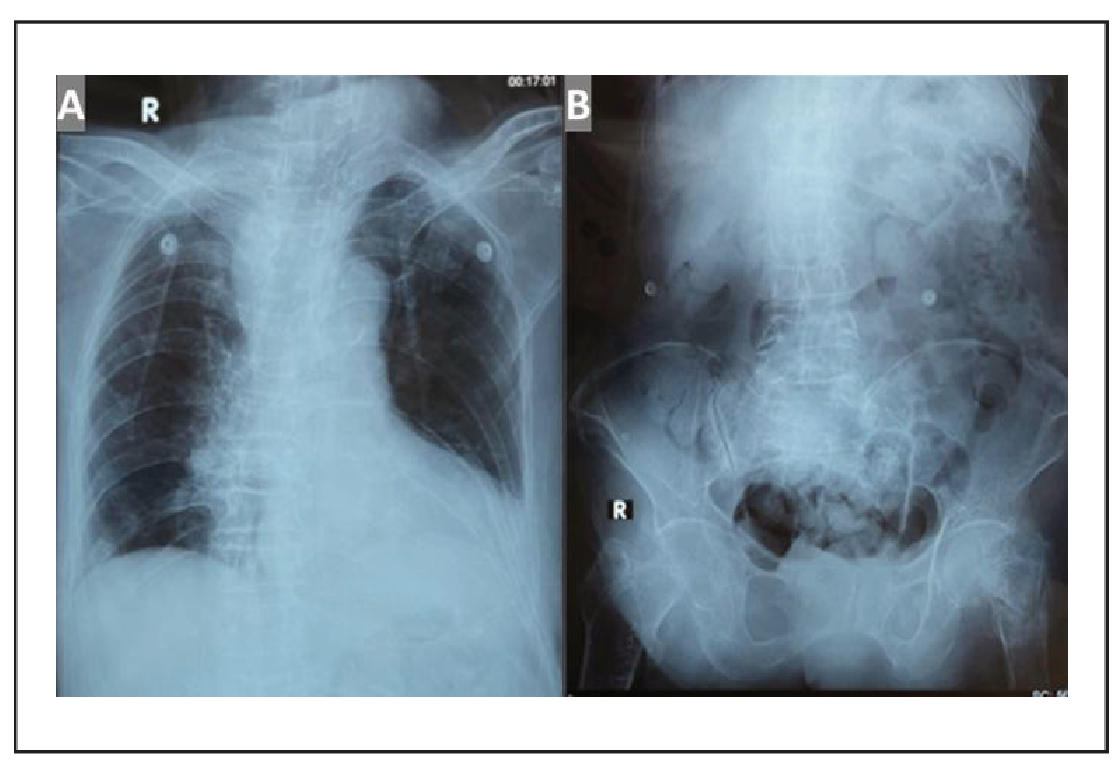

The complete laboratory findings are presented in Table 1. The deterioration of the comprehensive geriatric assessment (CGA) before and after the hip fracture is summarized in Table 2. Chest X-ray showed cardiomegaly and vertebral collapse (Figure 1A); abdominal X-ray revealed a comminuted femoral neck fracture (Figure 1B); and brain CT showed subacute-to-chronic left thalamic infarction with atrophy (Figure 2).

Figure 1. (A) Chest radiograph showing no pulmonary abnormalities, cardiomegaly with aortic atherosclerosis, and collapse of thoracic vertebral bodies (VTh) 2, 4, 5, 6, 7, and 8, accompanied by thoracic scoliosis with rightward convexity; (B) Abdominal X-ray showing a comminuted fracture of the left femoral neck. No evidence of ileus or pneumoperitoneum is observed.